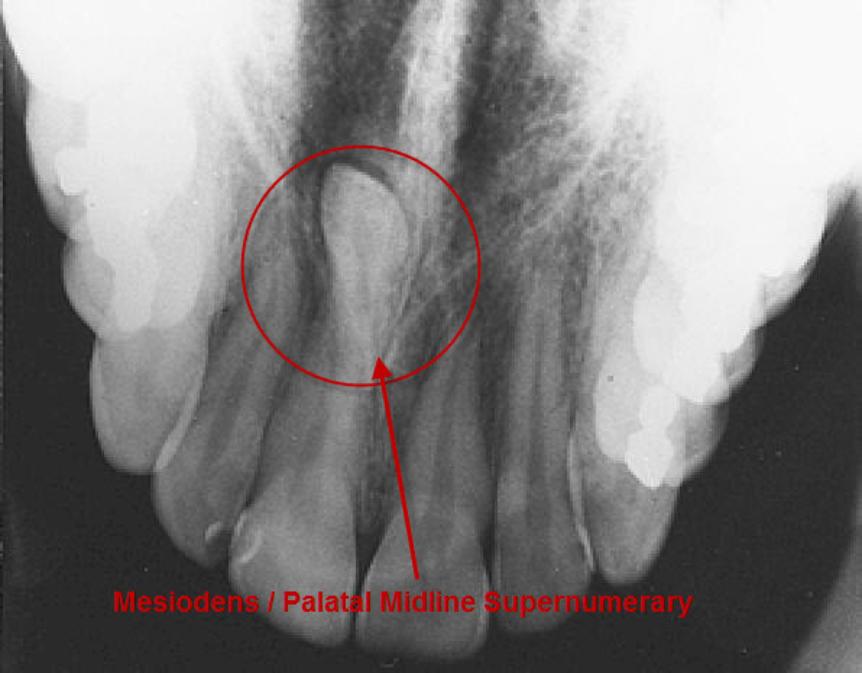

The prevalence of supernumerary teeth is reportedly between 0.15 – 3.9%. Most commonly, extra teeth are found between the upper central incisors (mesiodentes) or in the region of the premolars (paramolars) or very occasionally, behind the wisdom teeth (distomolars).

Supernumerary Teeth.

80 – 90% of all supernumerary teeth occur in the upper jaw. Half are found at the ‘front’ of the upper jaw. Mesiodentes frequently interfere with the eruption and alignment of the upper incisors. They can delay or prevent eruption, displace or rotate the erupting central incisors or less commonly, ‘bend’ (dilaceration) the developing roots of the central incisors so that tooth eruption is slowed / stopped, ‘eat away’ (resorption) the surrounding teeth, develop cysts around the crowns of the extra teeth (dentigerous cyst formation) and loss of tooth vitality. Rarely, the mesiodens can erupt into the nasal cavity